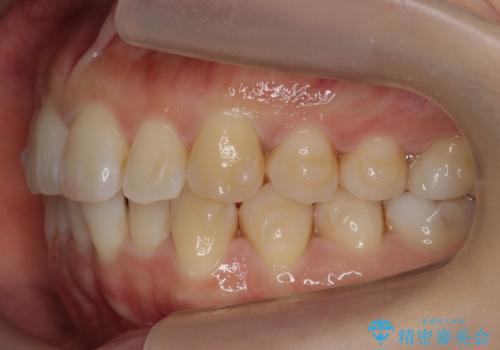

下の前歯のがたつき インビザラインで

- 前歯のがたつきを主訴に来院。

インビザラインで上下の前歯をわずかに削って並べました。

下の歯の叢生を並べると多少ブラックトライアングルがでることがあります。